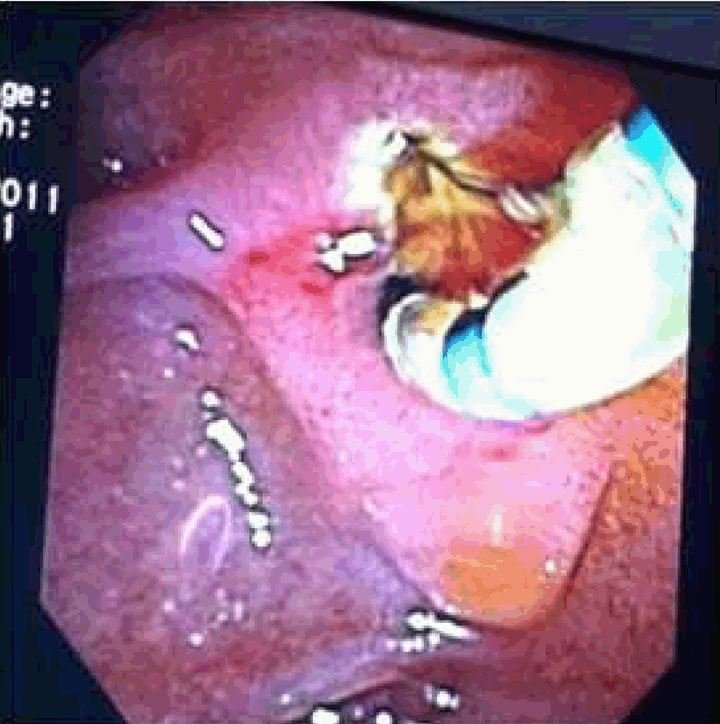

A 43-year-old female presented with severe right upper quadrant abdominal pain, nausea, vomiting and diarrhea for four days. Three years ago, she was admitted for cholecystitis, cholelithiasis and cholangitis requiring an endoscopic retrograde cholangiopancreatography (ERCP) with plastic stent placement for drainage. Unfortunately, the patient was lost to follow-up after initial plastic stent placement. On admission, she was afebrile and her liver function tests were normal. The ERCP was performed which revealed the distal end of the biliary stent, perforating proximal to the periampullary area causing a large choledochoduodenal fistula (Figure 1). The guidewire was successfully negotiated through the native papilla as well as the fistulous tract. No obstruction, mass or stone was noted. A sphincterotomy was done through the fistula (Figure 2) and through the actual sphincter at the ampulla (Figure 3). The sump was opened, swept clean with removal of abundant debris. Her abdominal pain completely resolved and patient clinically improved within 24 hours after the procedure. | ||||||